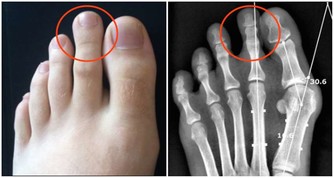

肝主筋,其華在爪,過子時不睡覺,會引起肝血不足,就出現筋痛,麻木,屈伸困難,痙攣抽搐,易造成灰指甲,缺鈣,髕骨軟化,癲癇病,骨質疏鬆等症。